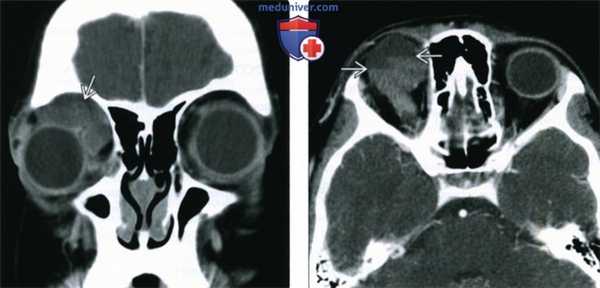

(Слева) У ребенка с периодически усиливающимся экзофтальмом при КТ с КУ в корональной проекции в верхнемедиальном квадранте переднего отдела глазницы определяется дольчатое образование от средней до низкой плотности, вызывающее смещение глазного яблока.

(Справа) При КТ с КУ в аксиальной проекции у этого же пациента в толще образования определяются множественные лакуны, содержащие жидкости различной плотности с отчетливыми уровнями. Более плотные длительно существующие продукты разложения крови оседают книзу.